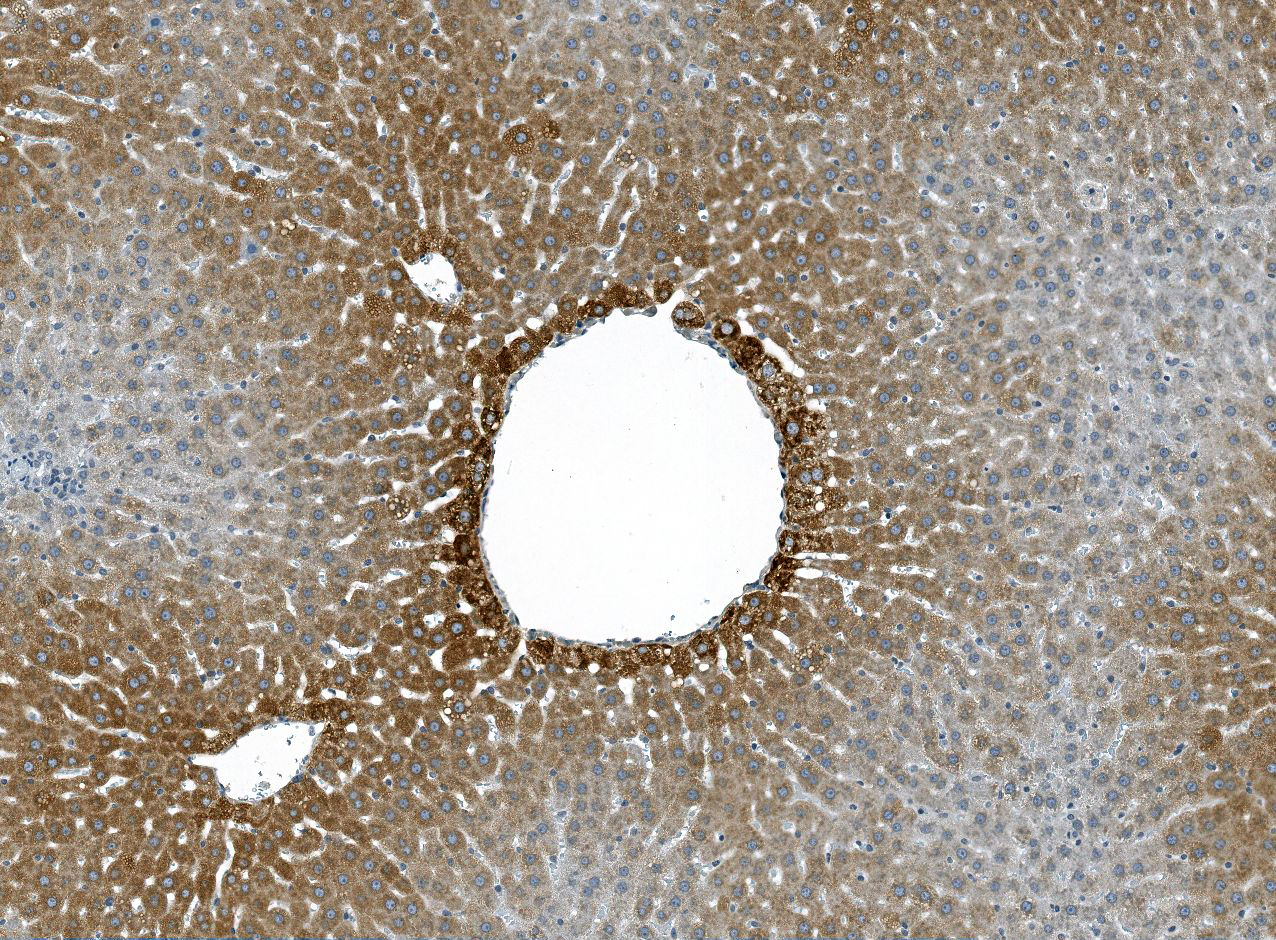

Cyp2E1: Immunoperoxidase staining of formalin fixed, paraffin embedded, TCDD treated rat liver showing a centrilobular cytoplasmic staining of hepatocytes.